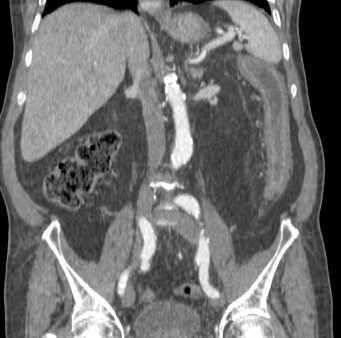

Paciente 89 años hospitalizada por dolor abdominal intenso y náuseas sin vómitos. El dolor es generalizado y no cede con tramadol.

A la exploración la barriga es blanda y depresible aunque empieza a defender en flanco derecho. No se observan masas ni megalias. Estreñimiento.

AP: Diabetes y dislipidemia. Insuficiencia cardiaca y HTA. Transplante renal hace 6 años.

TA: 80/60; FC 110 lpm; Sat O2 100%

Se realiza TC de abdomen en vacío y con contraste en fase portal:

Estamos ante un cuadro de isquemia intestinal en un paciente con bajo gasto cardiaco con afectación principal de asas intestino delgado, territorio vacularizado por la arteria mesentérica superior.